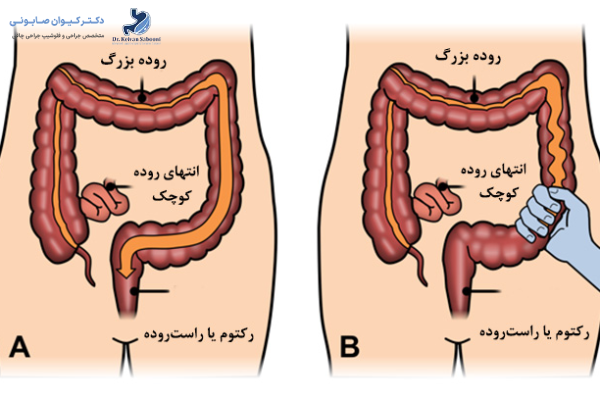

الگوی دفع در IBS سه شکل اصلی دارد:

- IBS با غلبه اسهال (IBS-D): دفعات مدفوع زیاد و آبکی است، گاهی همراه فوریت دفع.

- IBS با غلبه یبوست (IBS-C): مدفوع سفت و دفع دشوار یا با فاصلههای طولانی.

- IBS مختلط (IBS-M): دورههای اسهال و یبوست بهصورت متناوب رخ میدهند.

شناخت این زیرگروهها به انتخاب درمان درست کمک میکند، چون رویکرد دارویی و تغذیهای در هر نوع متفاوت است.